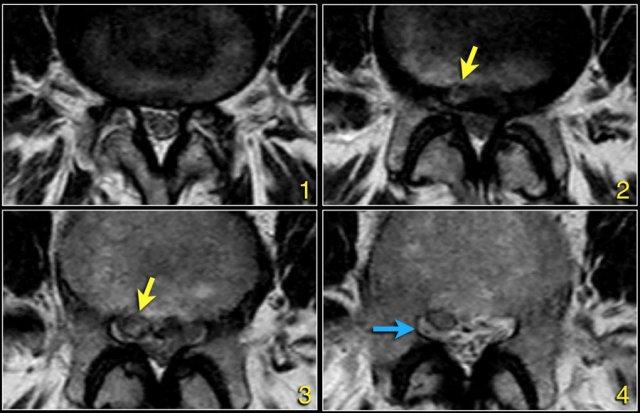

Các dấu hiệu tại các mức 1-4 như sau:

- Tại mức đĩa đệm, có hẹp ống sống tối thiểu do phình đĩa đệm và thoái hóa khớp mỏm khớp.

- Tại mức này, có hẹp ống sống nặng do phình đĩa đệm và thoái hóa khớp mỏm khớp.

Ngoài ra còn có rách vòng sợi (tăng tín hiệu) là nơi đĩa đệm thoát vị qua (mũi tên vàng). - Tại mức ngách bên, có thoát vị khu trú của chất đĩa đệm gây chèn ép rễ thần kinh L5 (mũi tên vàng).

Đây được gọi là thoát vị thực sự (extrusion), vì khoảng cách giữa các bờ của khối thoát vị lớn hơn khoảng cách tại nền. - Rễ thần kinh L5 bị chèn ép (mũi tên xanh dương) trong ngách bên.

Đĩa đệm thoát vị đã di trú xuống phía dưới và được thấy như một cấu trúc hình bầu dục nằm phía trước rễ thần kinh.

Đĩa đệm thoát vị không được bao bọc, tức là không được che phủ bởi các sợi của vòng sợi.